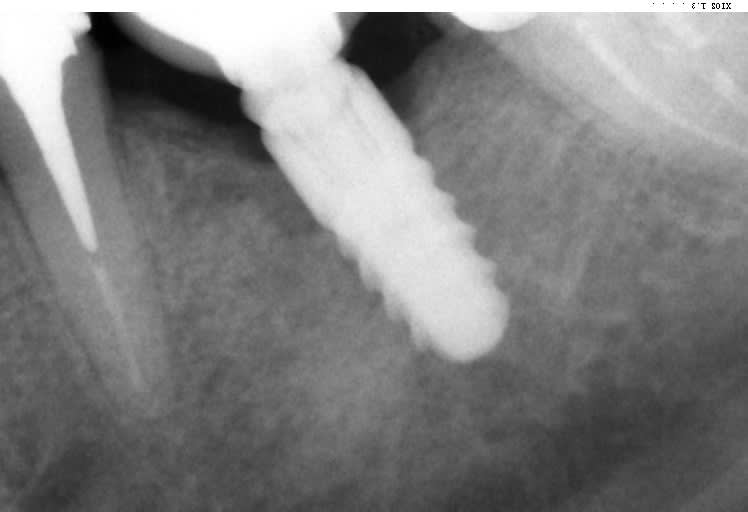

Bonjour, je ne parviens pas à identifier cet implant.

Implant posé par un confrère de St Omer il y a qq années et qui a mis fin à ses jours depuis.

TIOLOGIC DENTAURUM